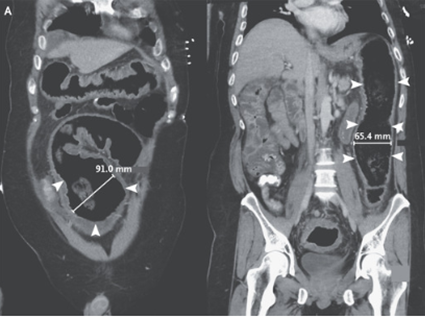

腹部CTではS状結腸および下降結腸の膨張を伴う汎結腸炎が明らかとなった。

経口および経静脈からMNZとVCMの投与が施行されたが、入院3日目にショック状態に至り、再度CT施行。

肝屈曲部の横行結腸拡大が120mmまで悪化していることが示され、「劇症C.difficile大腸炎による中毒性巨大結腸症」と診断された。